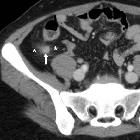

Crohn's disease in the appendix

CT

CT is commonly the first imaging assessment of those patients in the setting of acute abdomen, or it can be also applied to the reassessment of complications in patients with known Crohn disease. Common features include:

- mural hyperenhancement

- fat halo sign: submucosal fat deposition

- bowel wall thickening (1-2 cm), which is most frequently seen in the terminal ileum (present in up to 83% of patients)

- comb sign: engorgement of the vasa recta

- perienteric fat stranding

- affected bowel loops separated by focal/regionally increased fat (fibrofatty proliferation; creeping fat)

- strictures and fistulae, with upstream dilatation

- mesenteric/intra-abdominal abscess or phlegmon formation

- abscesses are eventually seen in 15-20% of patients